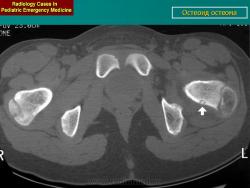

Остеоидная остеома (син. остеоид-остеома) - доброкачественное, как правило, одиночное новообразование, не превышающее I см в диаметре, имеющее четкие контуры и располагающееся в любой кости скелета, кроме костей черепа и грудины. Частота остеоид-остеомы составляет 2-3 % от общего числа опухолей костей и 12 % от общего числа доброкачественных опухолей костей. Большая часть больных - люди до 25 лет и моложе, причем мужчины болеют в два раза чаще женщин. Типичная локализация остеоидной остеомы-кости нижних конечностей, их диафизы и метафизы. Примерно половина опухолей обнаруживаются в проксимальном метафизе бедра и в большеберцовых костях. Эта опухоль обычно развивается в кортикальном слое кости, хотя не исключена и другая локализация, например субпериостальная зона и костномозговой канал. Остеоид-остеома в шейке бедра и мелких костях кистей и стоп располагается большей частью субпериостально. На долю позвоночника приходится 10 % этих новообразований, причем они находятся, главным образом, в дужках, а не в телах позвонков. В ключицах остеоидная остеома встречается исключительно редко.

При рентгенологическом исследовании остеоид-остеома обнаруживается как субкортикально расположенный участок окостенения, окруженный ободком остеосклероза, ширина которого увеличивается по мере прогрессирования опухоли. При этом центральная часть опухоли становится менее заметно. Граница между центральной светлой зоной и склеротическим ободком, отчетливая в ранний период, со временем стирается вследствие того, что центральная зона опухоли подвергается оссификации и обызвествлению, которые распространяются центробежно. Рост кортикальных и субпериостальных остеоид-остеом сопровождается также реактивным склерозом- Имеются указания и на то, что если новообразование растет в костномозговом канале, то в соответствующей кости развивается остеопороз. Обычно опухоль легко вылущивается из окружающей кости и макроскопически представляет собой мелкозернистую, красновато-бурую костную ткань. Остеоидную остеому, как правило, удаляют хирургическим путем. Рецидив возможен, но практически не встречаются. Если он и происходит, то спустя 10 лет и позднее после удаления первичного узла опухоли.

Рентгенологическая картина. На обзорных рентгенограммах очаг поражения характеризуется утолщением и уплотнением кортикального слоя кости вокруг небольшого литического гнезда.

Cancellous Osteoid Osteoma